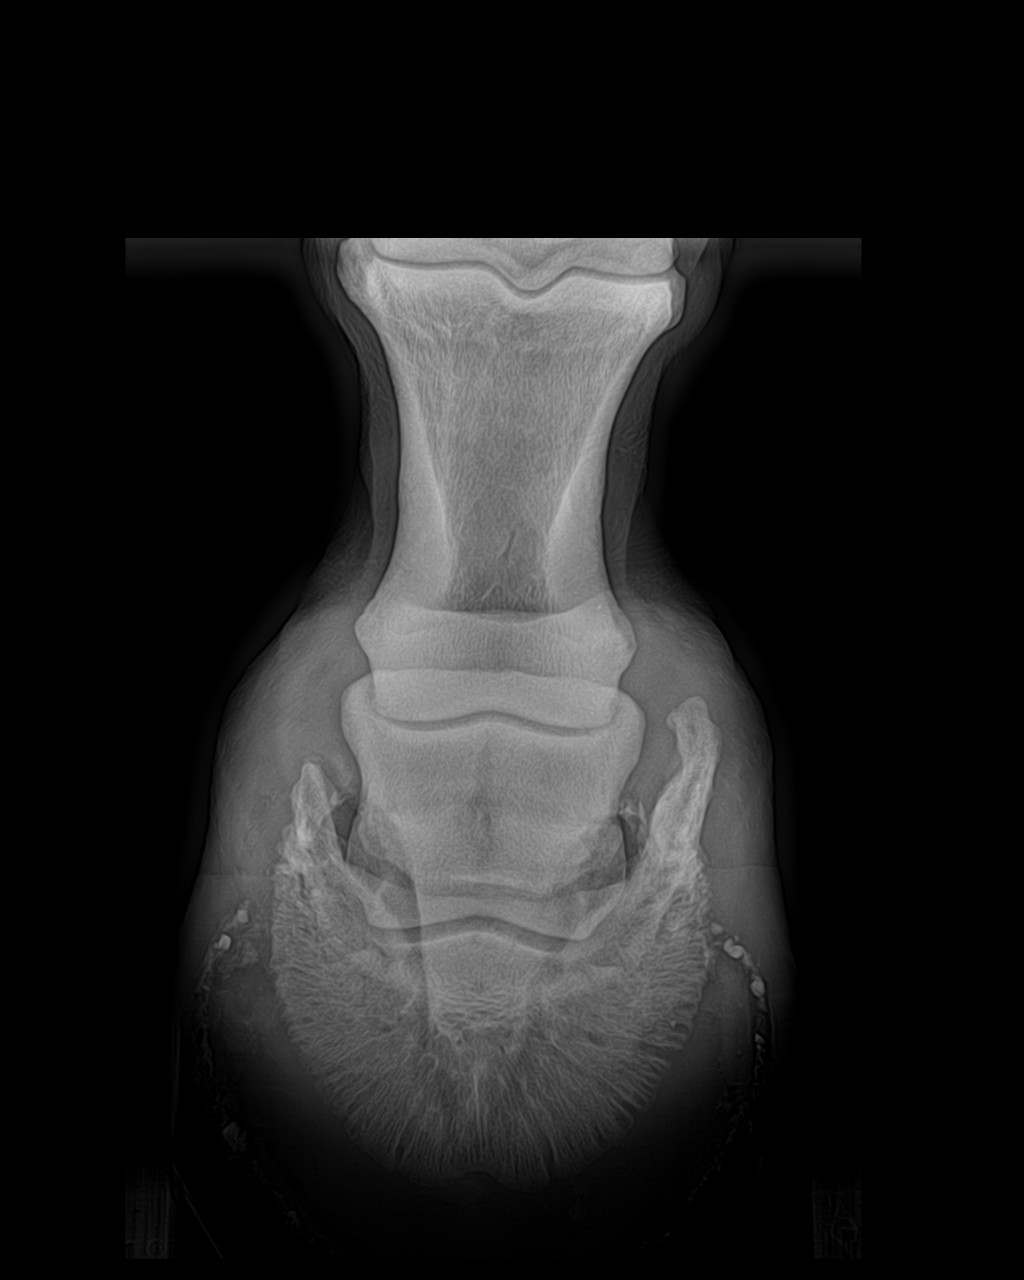

| Dire merci | juliie oui on aurait pu avoir pire, voici les derniers clichés radio du coup ( je sais qu'ils te font relativiser pour ton jaune ) AD ![]() ( On voit la petite pointe d'arthrose) AG ![]() (La on voit que la pointe d'arthrose est plus prononcée...Je sais si vous voyez, sinon j'entoure) Et là calcici...la calfifi...la Calcification ! ( Ça passe mieux sur un ton enjoué!) ![]() ![]() (Ce qui explique en grosse partie le côté trés sportif de ce journal ,heureusement qu'on bricole )erzebeth et takhan (mais je peux jamais t'identifier !!) Je vous prépare ça ( jsuis comme une folle ! J'adooooore les avants/aprés...sauf pr moi,là clairement ça va pas ds le bon sens ) |

| Dire merci | Verdict : pieds gauche : - calcifications n'ont pas bougées.. - arthrose en P3 Pied droit : RAS si ce n'est une pointe d'arthrose en P3 aussi mais minime. L'arthrose P3 à gauche est notre pb selon le véto, c'est archi fréquent chez les semi lourds et encore plus si on est sur du X comtois (jackpot!) Et a priori j'ai de la chance que ça arrive si tard... Bon on est pas foutu pour autant, il me conseille de le mettre en Duplo pour tester la différence de confort avec les chaussures. Il me conseille ensuite d'essayer le prévicox en confort pour nos balades, selon lui pas d'effet kiss cool pour l'estomac mais bcp de confort en plus et pas de culpabilité à avoir de l'aider avec ça pour nos sorties... Voilà, pour les Duplo, j'entends du très bon et du très mauvais, j'ai jusqu'au 2 novembre pour me faire un avis et décider de tester ou pas, car le MF du club en pose et il vient le 2. D'ici là je vais essayer des astuces plus cheap comme les semelles en mousse/tapis de gym ds ses chaussures pour vraiment comparer les différences pour l'amorti... O et S ont été geniaux. O très calme, dispo, et sage tout le long, il avait des pointes de tension parce que bcp de mouvement ds le club,il cherchait S du regard qui lui était complètement pepouse à jouer à " je t'ai volé ton nez,ne me bouffe pas le doigt" avec Céline. En plus elle fredonne souvent des musiques douces et ça a la pouvoir de détendre tt le monde...moi y compris.... J'étais tellement sur le fil que j'ai tilté a 17h que j'avais rien mangé depuis le matin 6h...alors au retour on a fait une pause brooting/ clémentine bien méritée pr tout le monde.. Pour ma part je suis positive,j'ai des choses à tester c'est le principal, ça me suffit à garder le sourire, mais j'ai une pointe d'incertitude sur cette fameuse boiterie à droite que je ressens depuis cet été au trot...la il n'a pas marqué à droite ni au pas, ni au trot, avec ou sans godasse mais je n'étais pas dessus... Est ce juste la gène gauche qui se répercute à droite ? Je me trompe pas sur les côtés de boiterie en général... Je vais tester tout ça et si je retrouve la boiterie je le filmerai ac cavalier pour en avoir le cœur net... Message édité le 21/10/20 à 10:21 |